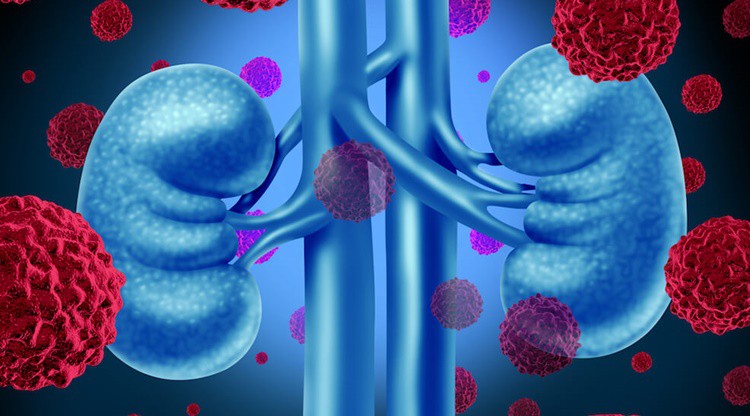

O Tumor de Wilms – O que é, Causas e Tratamentos que não devemos ignorar. Além disso, o Tumor de Wilms é um tipo raro de câncer de rim que afeta principalmente crianças. O câncer ocorre quando as células anormais em seu corpo se multiplicam de maneira incontrolável. Isso pode acontecer em qualquer idade, mas alguns tipos de câncer são exclusivos da infância.

O tumor de Wilms, também conhecido como nefroblastoma, é um desses câncer. Menos de uma em cada 10.000 crianças é afetada pelo tumor de Wilms nos Estados Unidos. Aproximadamente 500 crianças são recém-diagnosticadas a cada ano.

Embora raro, o tumor de Wilms é o tipo mais comum de câncer de rim em crianças e o quarto tipo mais comum de câncer infantil em geral. O tumor de Wilms é geralmente diagnosticado em crianças com cerca de 3 anos de idade. É raramente visto ou diagnosticado após a idade de 8, mas pode ocorrer em crianças mais velhas e adultos. Então, confira Tumor de Wilms – O que é, Causas e Tratamentos.

Causas Tumor de Wilms: Não está claro o que exatamente causa os tumores de Wilms. Até agora, os pesquisadores não encontraram ligações claras entre o tumor de Wilms e os fatores ambientais. Esses fatores incluem drogas, produtos químicos ou agentes infecciosos, tanto durante a gravidez da mãe quanto após o nascimento.